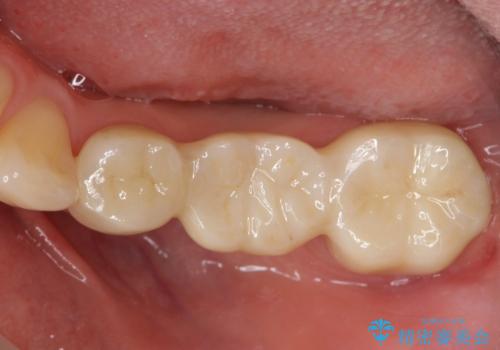

途中全体矯正をはさみ、根の向きが並行になった状態でブリッジを入れることができました。

- 36.3万円 (ジルコニアクラウン 10万円×3、仮歯1万円×3)費用は治療当時の料金となります